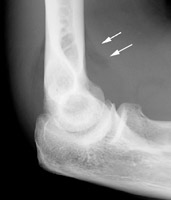

Diagnosis:Elbow effusion Discussion:Single lateral radiographs of the elbow which reveals the classic sail sign. This is an invaluable soft tissue finding in cases of intra-articular injury of the elbow. Fat is normally present within the joint capsule of the elbow, but outside the synovium. Typically "hidden" in the concavity of the olecranon and coronoid fossae, the fat is usually not visible on the lateral radiograph. However, injuries that produce intra-articular hemorrhage cause distension of the synovium and forces the fat out of the fossa, producing triangular radiolucent shadows anterior and posterior to the distal end of the humerus. When present in a patient with a history of acute trauma to the elbow, the fat pad sign indicates the presence of an intra-articular hemorrhage, which in turn is often associated with an intra-articular skeletal injury (usually the radial head in an adult). References: